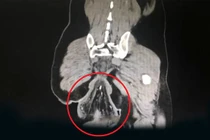

Tại bệnh viện, người đàn ông 55 tuổi được nội soi đại tràng, chụp CT bụng, CT ngực, chụp MRI vùng chậu. Dựa vào kết quả hình ảnh, bác sĩ chẩn đoán ông bị ung thư trực tràng 1/3 giữa, giai đoạn 3. Bệnh nhân được thực hiện hóa trị, xạ trị trước mổ. Sau đó, các bác sĩ phẫu thuật nội soi cắt đoạn đại trực tràng, nối đại tràng và trực tràng giúp người bệnh có thể đi tiêu bình thường.